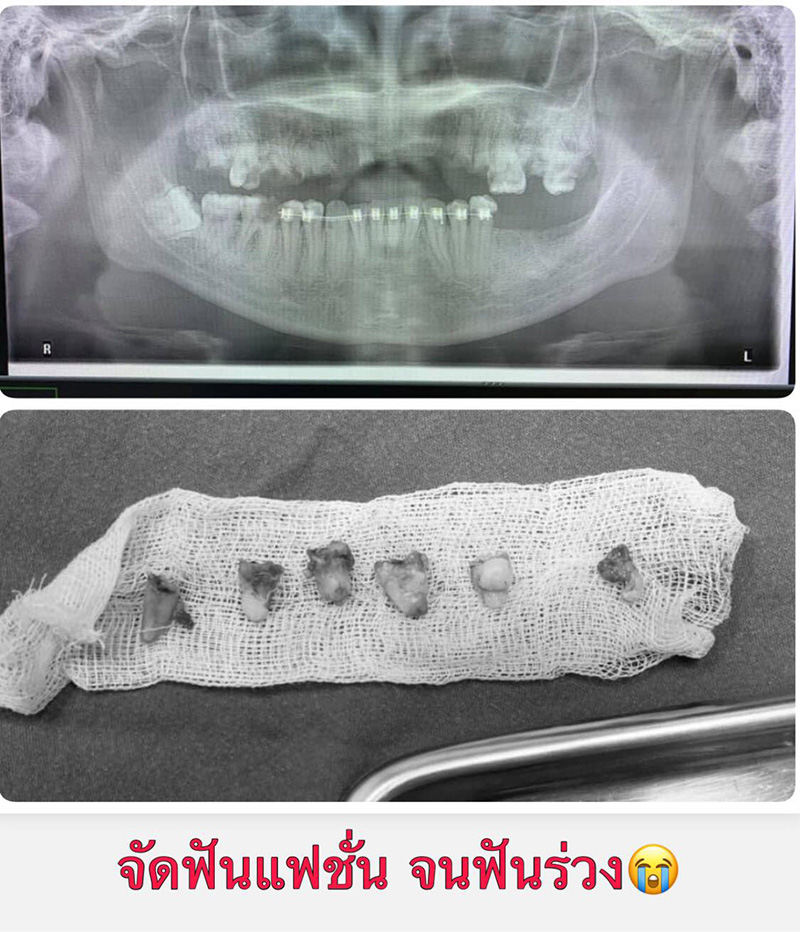

วันที่ 16 กุมภาพันธ์ 2564 เพจ Doctor กล้วย ได้มีการโพสต์เตือนภัยคนติดเหล็กดัดฟันแฟชั่น จนต้องถอนเกือบทั้งปาก โดยคุณหมอ เผยว่า เคสนี้เป็นคนไข้หญิง อายุ 30 ปี มาถอนฟันด้วยอาการปวด และมีหนองที่ฟันบน ตรวจพบว่า ฟันบนผุทั้งหมด ส่วนใหญ่เหลือแต่รากฟัน ดูจากฟิล์มเอกซเรย์ แทบไม่เหลือให้หมอรักษาแล้ว ฟันล่างผุเละ แถมยังติดเครื่องมือจัดฟันอยู่ หมอดูรู้เลยไม่ใช่ฝีมือหมอฟันแน่นอน จากการติดแบบมั่ว ๆ

#คนไข้ติดเหล็กดัดฟัน แบบไม่มีการเตรียมช่องปาก มานานเป็นปีแล้ว ฟันบนต้องถอนเกือบทั้งหมด ฟันล่างผุเละ และหินปูนหนามาก สรุปเกือบหมดปากที่ต้องทำฟันปลอมใส่ ทั้ง ๆ ที่อายุยังน้อย ดูกันนะ นี่คือผลของความ อยากติดเหล็กดัดฟัน โดยไม่คิดถึงผลเสียที่จะเกิดกับตัวเองไปตลอดชีวิตที่ไม่มีฟันเคี้ยวข้าว #อย่าหาทำ #จัดฟันแฟชั่นอันตราย แอดขอเตือน ขอบคุณข้อมูลและภาพจาก Doctor Supachai Sk ที่ช่วยส่งเคสมาเตือนสังคม